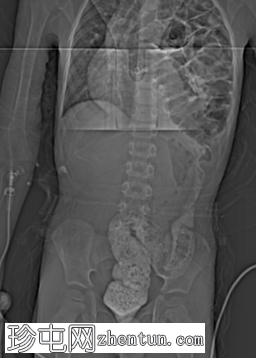

冠状面

非造影

左侧膈疝通过位于左膈中部的一个缺损形成,伴有纵隔向右侧移位,下方左塌陷。

脾脏、大肠和小肠均有疝气,同时伴有肠系膜上血管疝气。

胃位于下部,靠近主动脉分叉处。

在降结肠和直肠中可见先前荧光透视检查的残留造影剂。